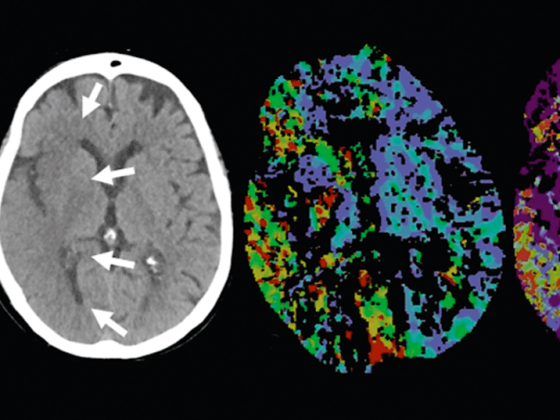

Der Erfolg der Schlaganfallbehandlung ist im Wesentlichen ­abhängig von der Zeit, die zwischen Symptombeginn und ­Rekanalisation des verschlossenen Gefässes vergeht. Hierfür ist es wichtig, dass schlaganfallverdächtige Symptome rasch erkannt werden und eine unverzügliche Zuweisung an ein ­spezialisiertes Zentrum erfolgt. Die Standardbehandlung des akuten Schlaganfalls ist die systemische Thrombolyse mit ­rekombinantem Plasminogenaktivator (rtPA) innerhalb von 4,5 Stunden nach Symptombeginn, wobei die endovaskuläre Revaskularisation gerade für proximale Gefässverschlüsse eine zu empfehlende Ergänzung zur systemischen Thrombo­lyse darstellt.